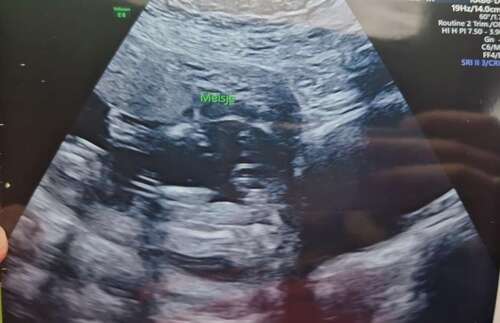

Is dit een 20-weken echo? Zijn die bij meer mensen zo onscherp? Want daar kunnen ze al die belangrijke details toch helemaal niet op zien? Bij ons zijn die echt veel scherper en die apparatuur was zelfs niet de beste vertelden ze.

Verder zou ik het wel bijzonder vinden als mensen hier op het forum aan een foto meer kunnen zien dan een opgeleide echoscopiste live op het scherm. Ze kijken zoveel belangrijke dingen na die amper te zien zijn, de kans dat ze het geslacht dan mis hebben is tegenwoordig echt heel klein (ik zeg niet dat het onmogelijk is, ik ken de verhalen 😉).

Maar.. om je vraag als leek te beantwoorden, ik zie ook een meisje voor zo ver ik er iets van kan zeggen ☺️

Ja, dit is een van de laaste foto's die ze gemaakt had. We vroegen nog om t geslacht, maar baby was erg druk en zij was vrij snel met foto maken. Rest was wel duidelijk gelukkig 😀

Maar dit is niet echt een antwoord op je vraag🙈 bij een meisje zou je 2 bobbeltjes moeten zien en bij een jongen 2 bobbeltjes met een puntje.